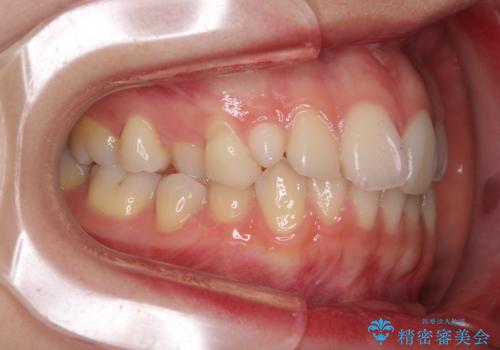

- 前歯のクロスバイトや残存している乳歯を気にして来院された患者様です。

上顎骨の幅が下顎骨よりも小さいので、拡大装置により骨幅を広げて上下関係を改善し、その後インビザラインにて歯並びを整えることとしました。

上下の骨幅を改善したことで、スムーズに歯列矯正を行うことができました。

通院ペースが守れず治療期間が長くかかってしまいました。